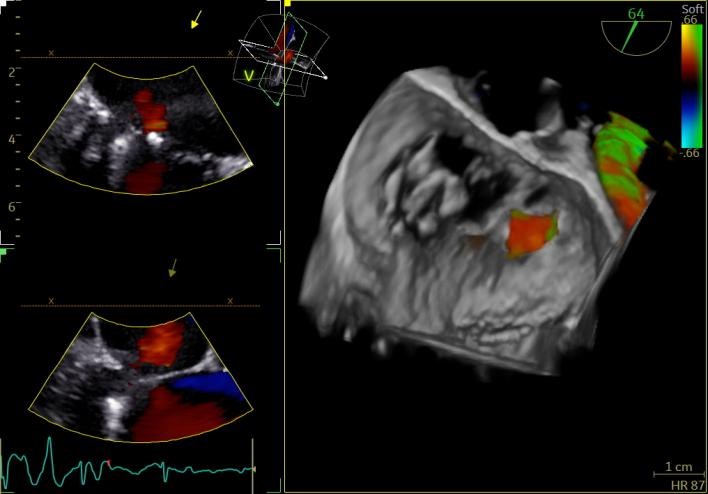

团队凭借丰富经验,拉开了一场精密手术的帷幕。在李剑平副院长的带领下,心超团队通过经食道超声在术中精准“导航”,麻醉科、胸外科、ECMO团队、ICU、血管外科等多学科专家紧密协作,金骁琦主任医师团队反复调整毫米级的介入位置,历时两小时成功完成修复!

术后复查心超显示,二尖瓣反流降至微量!手术效果立竿见影,患者心脏功能显著改善,胸闷气喘等症状显著缓解。

TEER也叫经皮二尖瓣钳夹术,是目前治疗重度二尖瓣关闭不全最成熟可靠的微创介入技术之一。经股静脉入路穿刺房间隔后,在超声引导下用特制的夹子钳夹住二尖瓣的前、后瓣叶并使之接合从而减少或消除二尖瓣返流,对团队协作、超声导航及操作精度的要求极高。此次手术的成功开展,充分彰显了我院多学科协作(MDT)的强大实力和心血管内科在微创介入领域的技术水平。